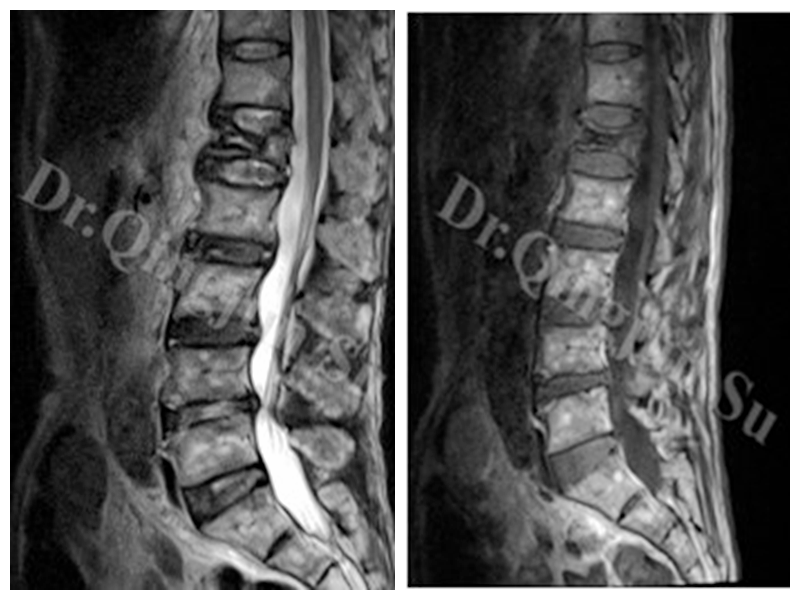

④在核磁上:诊断率最高,IVC主要有两种表现:当裂隙内主要是液体时,在T1上低信号,T2上高信号。(见上图)

当裂隙内是气体时,T1和T2相上均为低信号(见上图)。